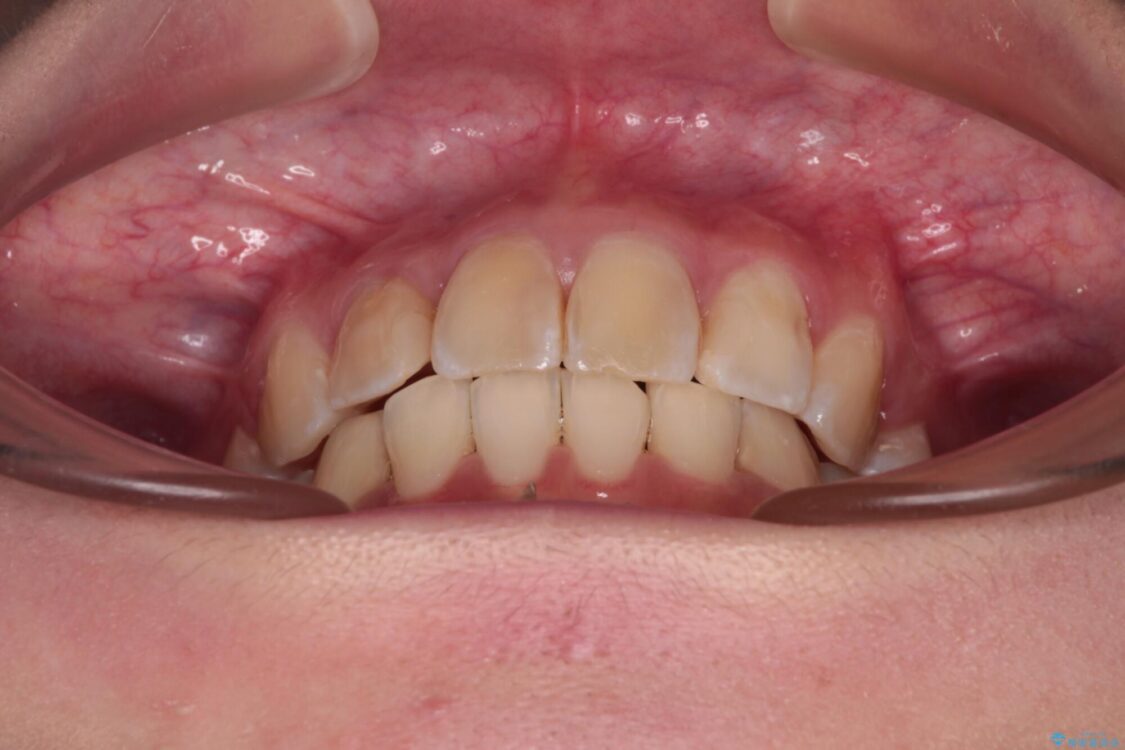

治療後

• デコボコと深い咬み合わせ ワイヤー装置での抜歯矯正 治療後画像

治療後について

咬み合わせが深く、そのままでは上顎の抜歯スペースが閉じきらない可能性があったため、治療初期から深い咬み合わせを改善させるように試みました。

実際にはなかなか改善されず、当初予定よりも治療期間がやや長期化してしまいました。